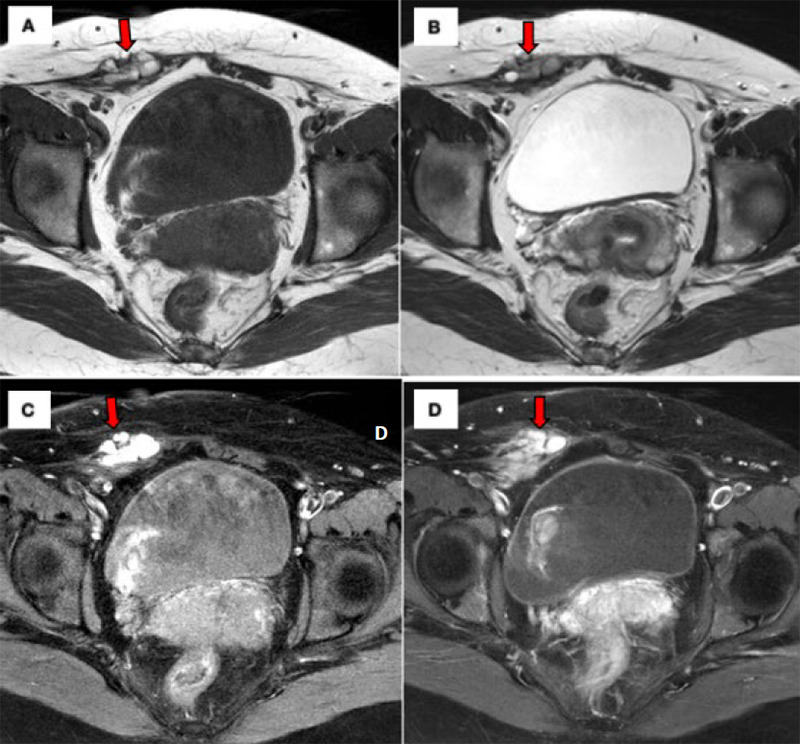

Abdominal wall endometriosis (AWE) is a rare type of endometriosis, with an incidence ranging from 0.1% to 0.4%. It requires a high index of suspicion to avoid delays in diagnosis and treatment. This case is rather special because AWE occurred without a history of abdominal surgery or pelvic endometriosis. Herein, we report the case of a 48-year-old para-3 woman with localised cyclical abdominal pain associated with abdominal distension. On assessment during menstruation, there were localised tenderness at the right suprapubic area and a non-tender suprapubic mass corresponding to a 14-week-sized gravid uterus. An ultrasound revealed the presence of a heterogeneous hypoechoic lesion at the subcutaneous layer of the right suprapubic region sized 1.8×3.2×4.4 cm with poor demarcation. There were also multiple uterine fibroids varying in size and location. She underwent exploratory laparotomy, total abdominal hysterectomy with bilateral salpingo-oophorectomy and abdominal wall mass resection. Intraoperatively, the right abdominal wall mass measuring 6x5 cm and involving the subcutaneous layer was found to adhere to the rectus sheath with some chocolate-stained areas without connection to the peritoneal cavity. Additionally, multiple uterine fibroids were noted. There was no pelvic endometriosis, and the other pelvic organs were normal. The histopathological diagnosis of the abdominal wall mass was endometriosis. AWE should be one of the differential diagnoses even in the absence of previous surgery when encountering a patient with an abdominal wall mass especially when it is related to the menstrual cycle.